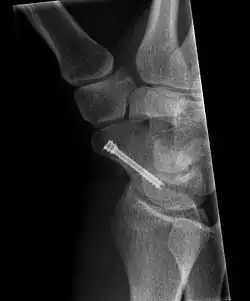

The scaphoid can be slow to heal because of the limited circulation to the bone. Fractures of the scaphoid must be recognized and treated quickly, as prompt treatment by immobilization or surgical fixation increases the likelihood of the bone healing in anatomic alignment, thus avoiding mal-union or non-union.[6] Delays may compromise healing. Failure of the fracture to heal ("non-union") will lead to post-traumatic osteoarthritis of the carpus.[1]: 189 One reason for this is because of the "tenuous" blood supply to the proximal segment.[3] Even rapidly immobilized fractures may require surgical treatment, including use of a headless compression screw such as the Herbert screw to bind the two halves together.

Healing of the fracture with a non-anatomic deformity (frequently, a volar flexed "humpback") can also lead to post-traumatic arthritis. Non-unions can result in loss of blood supply to the proximal pole, which can result in avascular necrosis of the proximal segment.

Scaphoid fractures may be difficult to diagnose via plain x-ray. A repeat x-ray may be required at a later date, as might cross-sectional imaging via MRI or CT scan.[6]